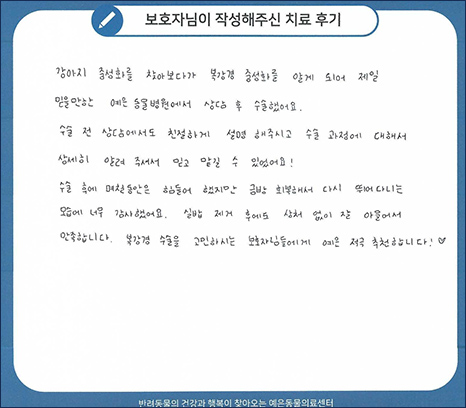

치료 후기 01

강아지 중성화를 찾아보다가 복강경 중성화를 알게 되어 제일 믿을만한 예은동물병원에서

상담 수 수술했어요. 수술 전 상담에서도 친절하게 설명 해주시고 수술 과정에 대해서 상세히 알려 주셔서

믿고 맡길 수 있었어요! 수술 후에 며칠동안은 힘들어 했지만 금방 회복해서 다시 뛰어다니는 모습에

너무 감사했어요. 실밥 제거 후에도 상처 없이 잘 아물어서 만족합니다.

복강경 수술을 고민하시는 보호자님들에게 예은 적극 추천합니다.